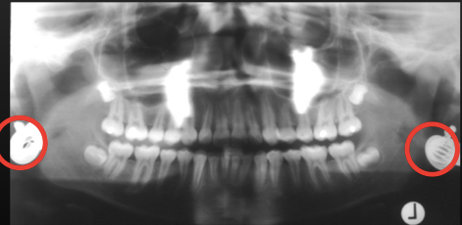

What is this positioning error?

Teeth behind focal trough

- When teeth are behind focal trough they look more enlarged – magnified horizontally

- Cant see the spine at all because its out of the focal trough